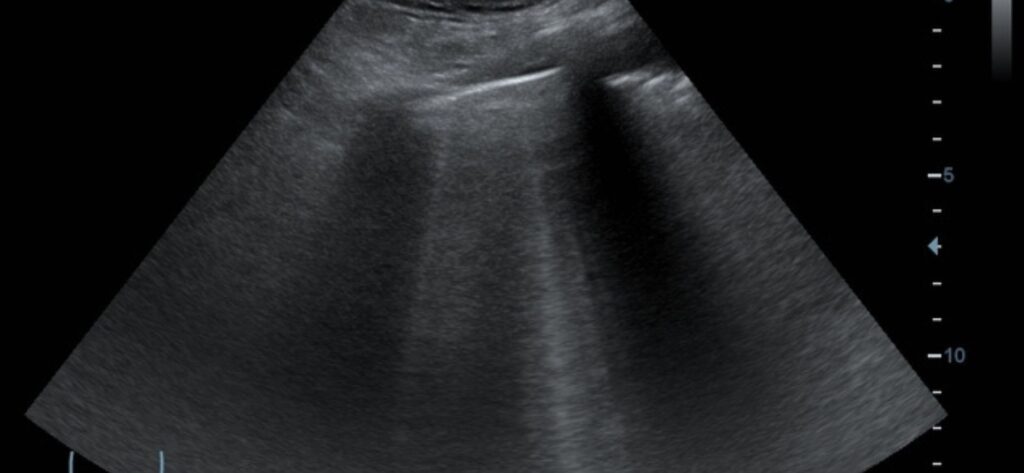

Ecografia polmonare

È utile? L’ecografia del polmone non è un esame che si esegue routinariamente nella pratica elettiva in radiologia o negli ambulatori di radiologia. Tuttavia, il